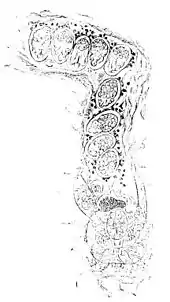

Fig. 12.—Burrow of Itch-Insect (Sarcoptes scabei).—Female depositing eggs. The eggs lying next to the insect consist partly of an homogeneous, partly of a granular mass: in those distant from the insect embryos are already developed, and at the entrance of the furrow a moving acarus is seen.